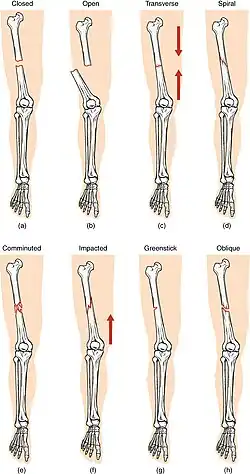

(a) closed fracture

(b) open fracture

(c) transverse fracture

(d) spiral fracture

(e) comminuted fracture

(f) impacted fracture

(g) greenstick fracture

(h) oblique fracture

In orthopedic medicine, fractures are classified in various ways. Historically, they are named after the physician who first described the fracture conditions; however, there are more systematic classifications as well.